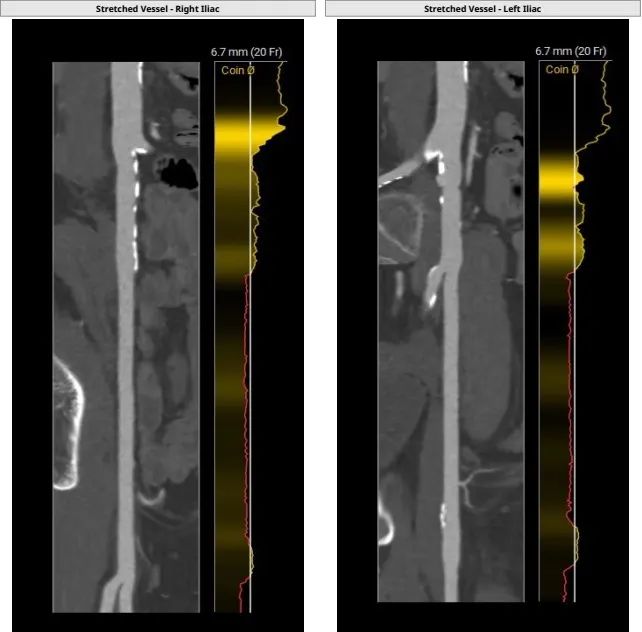

入路情况:

主动脉弓部走行较平缓,可见少许钙化斑块,主动脉弓部三根毛开口未见明显狭窄征象、未见发育变异,胸主动脉、腹主动脉走行稍迂曲,可见少许钙化斑块,管腔未见明显狭窄,双侧髂动脉-股动脉走形稍迂曲,可见钙化斑块,管腔未见明显狭 窄,综合考虑,推荐右侧股动脉做为主入路。右侧股动脉穿刺水平管腔直径约为7.9mm,右侧股动脉分叉约在股骨头中下1/3水平。